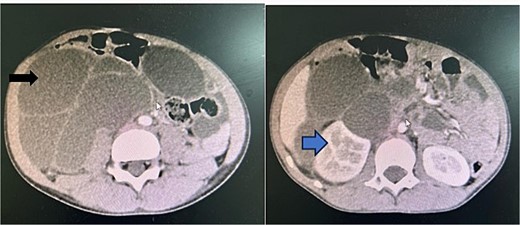

Contrasted abdominal pelvic computed tomography was done. A large well-defined homogenous enhancing cystic mass lesion with internal septations and lobulated with outlines of peritoneal cavity extending from the below right renal inferiorly to the mid of the lower abdomen. Occupying the right iliac fossa and reaching the pelvis. It measured 13.1 × 15.5 cm with ipsilateral hydronephrosis and mild intrahepatic duct dilatations. The pancreas and the spleen appear normal, left kidney has normal size shape and secretory functions. Paraaortic regions are normal. The bowel loops are unremarkable. Urinary bladder appears normal (Fig. 2).

A contrasted preoperative abdominal pelvic computed tomography Image with IV contrast. The black arrow shows an intraabdominal multiseptated fluid cyst. The blue arrow shows hydronephrosis of the right kidney as the result of the pressure effect of the mass.